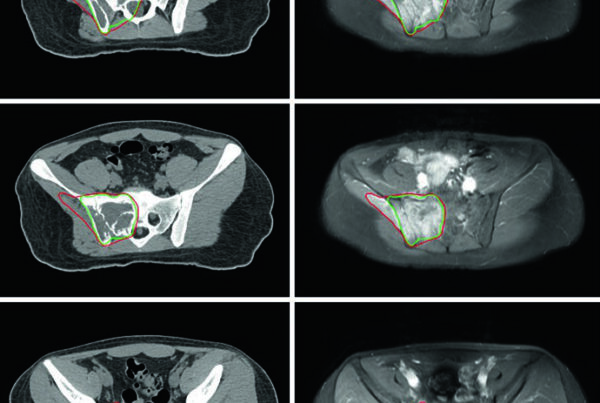

As figuras 26.3 a 26.5 reforçam como essa estratégia aparece no tratamento real. O capítulo mostra um campo pélvico inicial com IMRT, depois o boost vesical sequencial, e finalmente um exemplo de quimiorradioterapia concomitante com IMRT limitada à bexiga. O valor dessas vinhetas clínicas está em mostrar que a escolha entre pelve completa e bexiga isolada não é abstrata; ela muda o contorno, o PTV e a relação com reto, próstata e alças intestinais.

Nos pacientes linfonodo-positivos, a fase inicial pode incorporar um simultaneous integrated boost para escalar dose em adenopatia macroscópica. A referência institucional é 5625 cGy em 25 frações diárias de 225 cGy sobre doença nodal grosseira, com PTV definido como GTV + margem de 5 mm e sempre respeitando a tolerância do tecido normal. As figuras 26.6 e 26.7 fecham o capítulo exatamente com esse tipo de caso, mostrando como o planejamento muda quando a doença extrapola a parede vesical e alcança linfonodos visíveis.